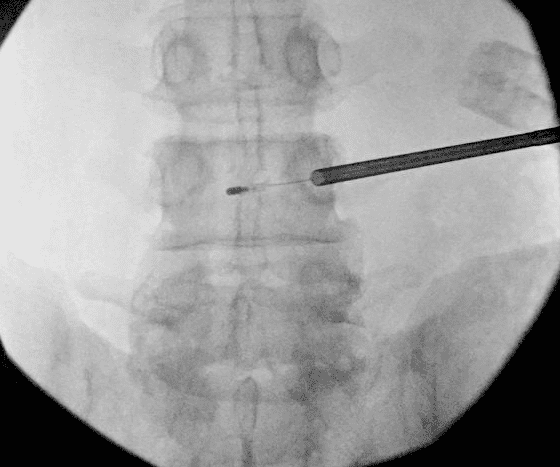

procedures

Spinal Cord Stimulation Explantation and Chronic Pain: A Systematic Review and Technology Recommendations